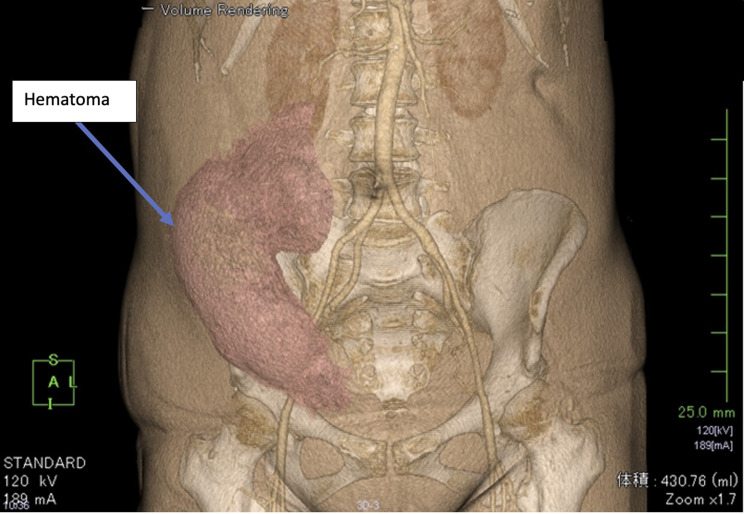

Case presentation: A 40-year-old female underwent bilateral ultrasound-guided rectus sheath block and transversus abdominis block following laparoscopic cholecystectomy. After the operation, a large, painful hematoma was identified with a volume estimated at 430 mL. Investigation of the bleeding site by CT scan showed that the hematoma was subcutaneous and in an area with multiple venous and arterial branches. Identification of the responsible vessel appeared difficult; however, on discussion with the radiologist, bleeding from a cutaneous (or deeper) vessel from the block or surgical (trocar or needle) injury was included in the different diagnosis. The superficial epigastric artery was considered the most probable source because it was the closest to the hematoma.